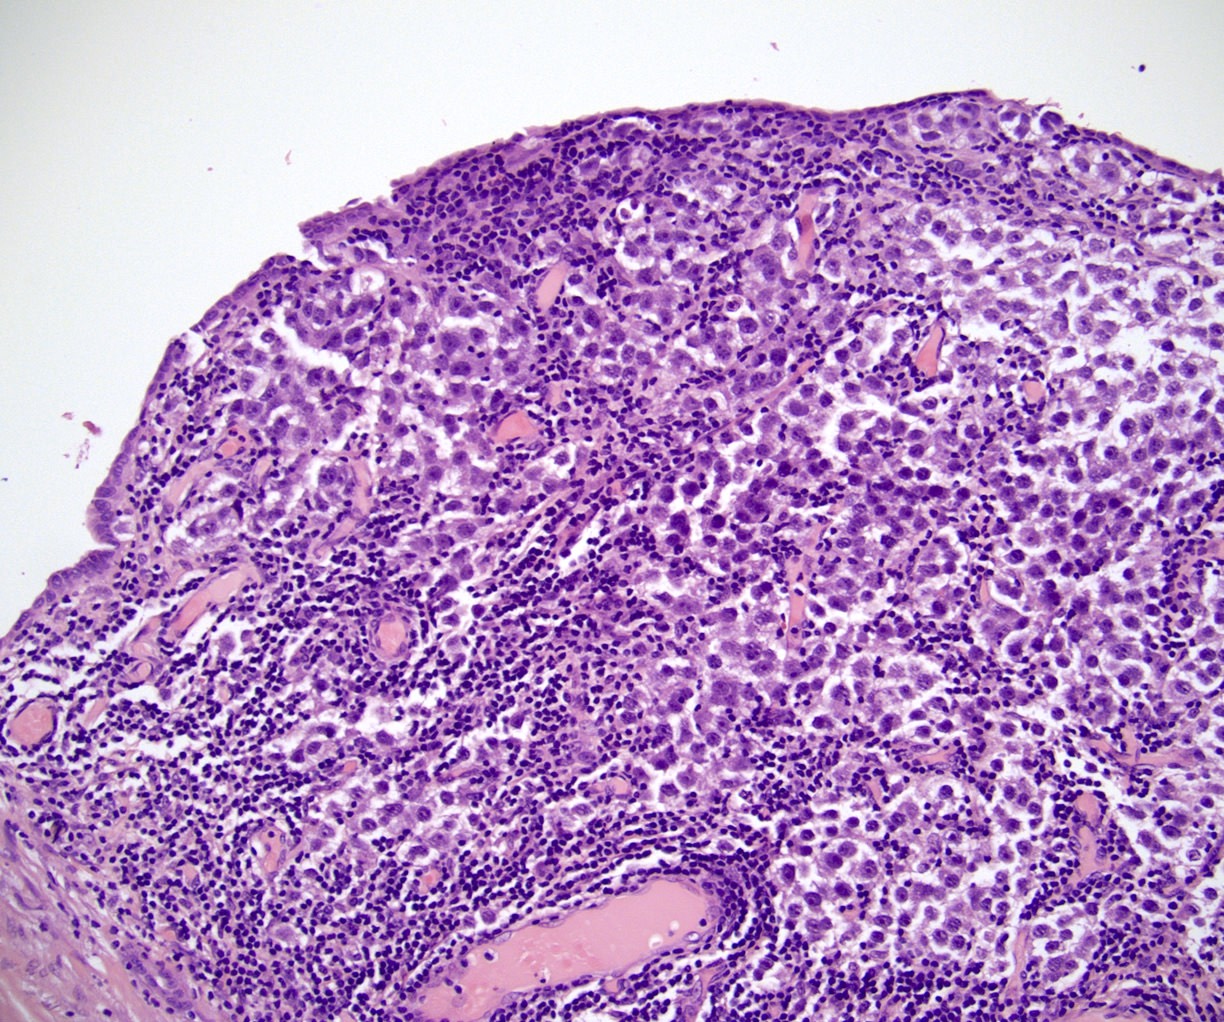

Microscopic (histologic) images

Testis & epididymis - Staging Board review style question #2

The postpubertal teratoma shown in the gross photo is 1.7 cm and is confined to the testis and did not have lymphovascular invasion. Which is the correct pT category?

Board review style answer #2

A. pT1. Postpubertal germ cell tumors that are confined to the testicular parenchyma and lack lymphovascular invasion are pT1, pT1a or pT1b. Pure seminoma is stratified as pT1a and pT1b based on a 3 cm threshold. Nonpure seminomas are not stratified and therefore this tumor is pT1.

Comment Here Reference:

Testis & epididymis - Staging